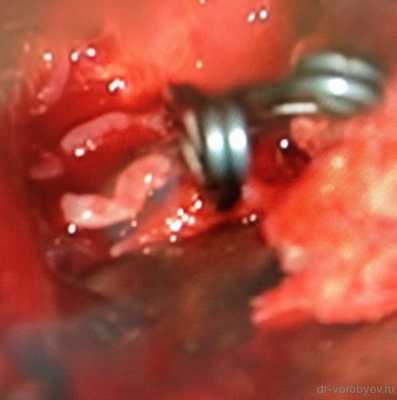

Интраоперационное фото клипированной аневризмы левой средней мозговой артерии.

Представляю вниманию фото 2 аневризм — основной артерии и развилки средней мозговой артерии, с которыми пришлось столкнуться в нашей клинике за последние 2 недели.

Мешотчатая аневризма развилки основной артерии

Мешотчатая аневризма развилки левой средней мозговой артерии. Аневризма и ветви М2 обведены шариковой ручкой.